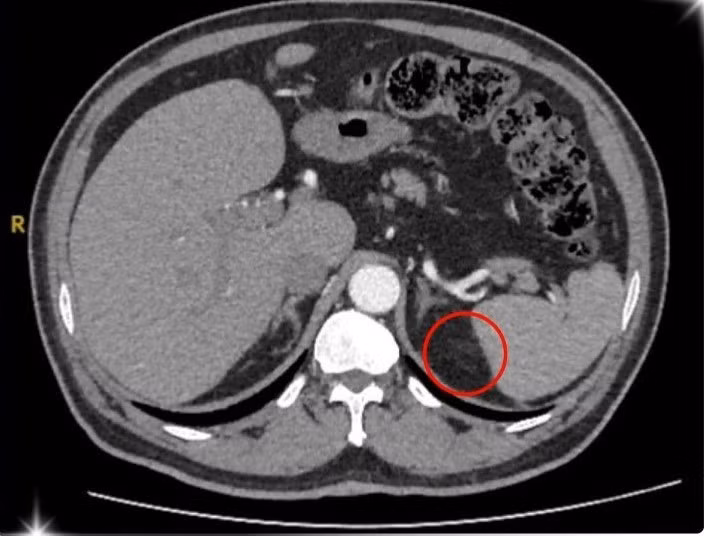

U tuyến thượng thận trên phim chụp - Ảnh BVCC

Sau quá trình kiểm tra kỹ lưỡng và chụp hình ảnh MSCT 160 lát vùng ổ bụng của bệnh nhân u tuyến thượng thận, ông T. được xác định mắc phải hội chứng Conn (hay còn gọi là cường Aldosterone tiên phát) – một bệnh lý hiếm gặp do khối u nhỏ ở vỏ tuyến thượng thận gây ra.